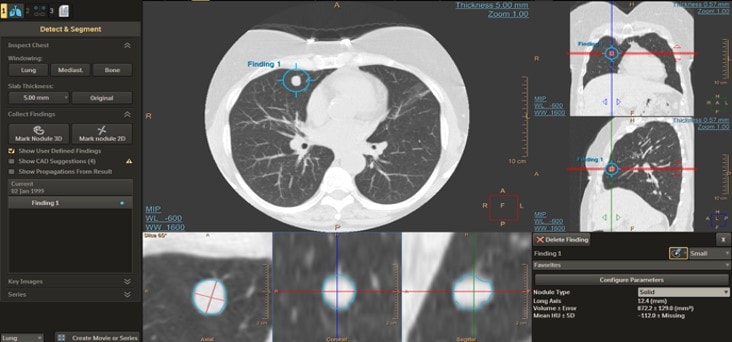

Die Herausforderung der konsistenten Erkennung wird durch strukturierte und automatische Auswertung auf der AVW – Advanced Visualisation Workstation unterstützt (z. B. LungRADS), was die Vergleichbarkeit erhöht und Folgeentscheidungen erleichtert.

Die Advanced Visualization Workspace (AVW) von Philips unterstützt Radiologen bei der effizienten Auswertung von Low-Dose-CTs im Rahmen des Lungenscreenings. Dank der Integration des ClearRead-Algorithmus von Riverain werden Lungenknoten schneller erkannt und charakterisiert. Über den Philips AI Manager lassen sich zudem weitere Algorithmen unterschiedlicher Hersteller einsetzen – nahtlos integriert in den klinischen Workflow. So profitieren Anwender von automatischer Lungen- und Lappensegmentierung, standardisierten Workflows nach Lung-RADS oder den Fleischner-Empfehlungen, einem integrierten Risikorechner sowie der automatischen Bereitstellung der Ergebnisse im PACS. Das Ergebnis: konsistente Befunde, höhere diagnostische Sicherheit und spürbare Zeitersparnis.